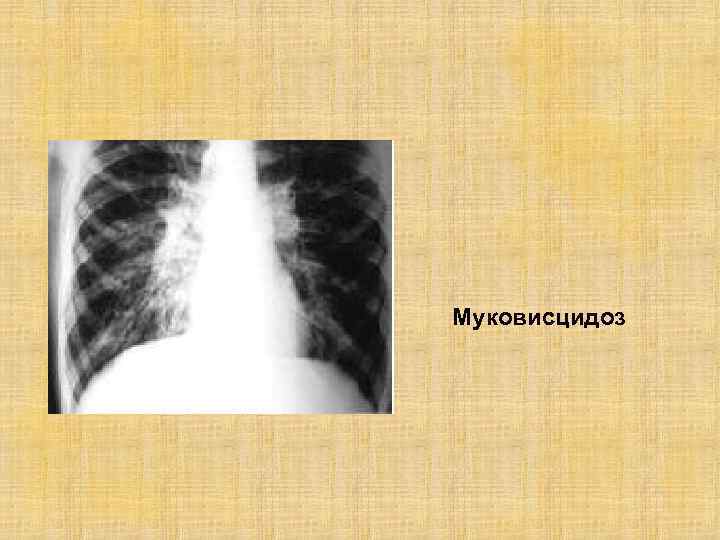

Муковисцидоз